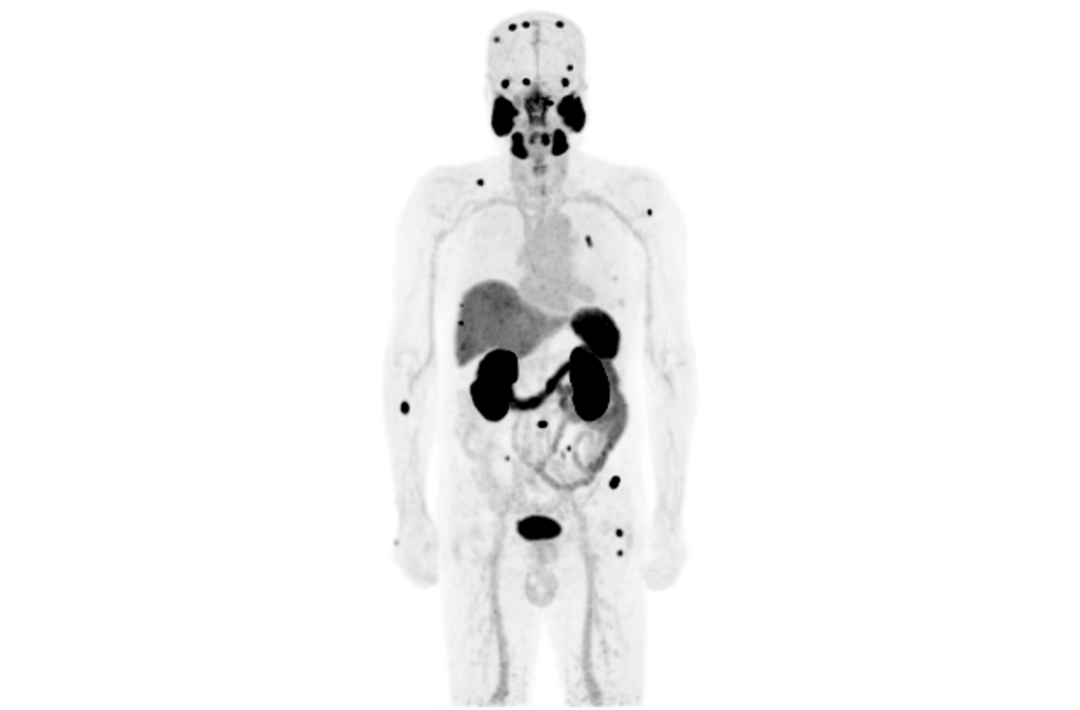

Compared with the conventional PET system with AFOV ranging between 20cm and 25cm, the 32cm long AFOV not only improves the sensitivity of the system, but also basically covers main organs of the whole body and the regional lymphatic system where metastasis may occur, and makes it possible to realize cancer TN staging in one bed position.

Traditionally, a PET/MR scan of a tumor patient takes about 35 to 50 minutes. The long AFOV can further optimize the PET/MR tumor scanning scheme. In other words, it can optimize the decision about whether to scan the whole body based on whether the tumor patient has regional lymphatic metastasis after regional PET/MR scan, potentially saving scan time for patients without metastasis.

In August 2019, Peking Cancer Hospital introduced United Imaging Healthcare's integrated PET/MR to make an in-depth exploration and optimization of cancer TNM staging under long AFOV. More than 500 examples of scanning various organs proved that long AFOV PET/MR could greatly increase the scan range over one bed position and improve the efficiency of cancer TNM staging.

The following are the cases of optimized TNM staging of breast cancer, esophageal cancer, prostate cancer and other diseases under the long axial field of "spatio-temporal integration" ULTRA-clear TOF PET/MR.  Thanks to Capital Medical University Xuanwu Medical Treatment for providing the image.